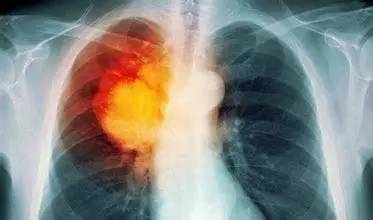

肺癌的小知识

鳞癌: 40%~50% 大多50岁以上,男性占多数。 与吸烟关系非常密切。 一般生长较缓慢,病程较长,远处转移少,较晚发生转移。 手术切除率较高,对放疗和化疗的敏感度较差 腺癌 约20% 女性多见,发病年龄较鳞癌、小细胞癌年轻10岁左右。 与吸烟无密切关系。 富含血管,转移较鳞癌早,易转移及胸膜,引起胸腔积液。对放疗和化疗敏感性也差,但可能优于鳞癌。 大细胞癌 约9% 老年男性多见。 与吸烟有关。 恶性度高,转移较早。 以手术治疗为主。 小细胞癌 约10%~20% 中老年人为主。 80%以上为男性。 与吸烟关系密切。 生长快,侵袭力强,远处转移早。 对放疗和化疗高度敏感。 此外,根据肺癌肿瘤生长的部位,肺癌还可分为中央型肺癌和周围型肺癌。前者更靠近人体的中线,后者则生长于离人体中线较远的位置。

中央型肺癌:约占3/4,以鳞癌和小细胞癌多见,症状如咳嗽、咯血、喘鸣等较多见。 周围型肺癌:约占1/4,以腺癌多见症状较少,甚至没有症状,易延误诊断。